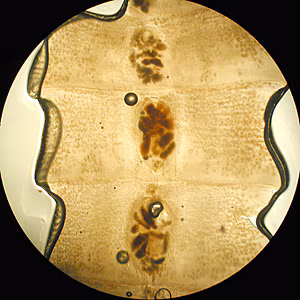

Case #172 – January 2006

This case was kindly contributed by the Florida Department of Health.